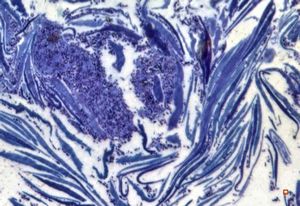

M,68y. | auditory meatus … otitis externa mycotica

M,68y. | auditory meatus … otitis externa mycotica - (toluidine-blue- stained semithin section)